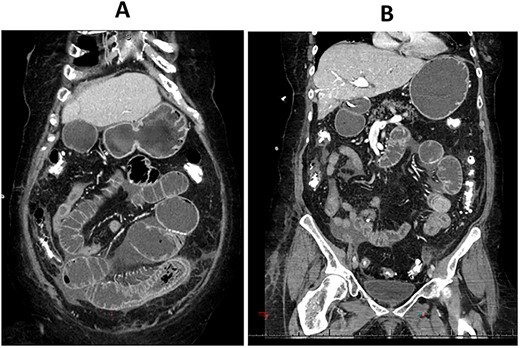

CT enterography: axial views demonstrating dilatation of the bowel loops in the left lower quadrant associated with bowel thickening and collapsed small bowel loops distally.

The patient is a 71-year-old white female with a past medical history of PSC who underwent orthotopic deceased donor liver transplant in 2006 with a Roux-en-Y hepaticojejunostomy biliary anastomosis. Cholecystectomy was performed to the donor liver. Her course has been complicated over the years by recurrent cholangitis requiring a permanent percutaneous biliary drainage tube. The patient had a liver biopsy in 2011 which showed recurrent PSC, but the patient refused any further liver transplants. Her daily immunosuppressive regimen consisted of cyclosporine 25 mg. Thirteen years after the deceased donor liver transplant, the patient presented to our emergency department with abdominal pain for a week which was associated with abdominal distention and nausea. Her liver function tests and complete blood count were normal on admission. Computed tomography (CT) scan of her abdomen and pelvis with intravenous contrast demonstrated focal dilatation of proximal jejunal bowel loop at the site of anastomosis with air-fluid/debris level (Supplementary Figure 1). She was admitted to the hospital and was initially managed conservatively with nasogastric tube suction, bowel rest and intravenous fluid hydration. A small-bowel follow-through study was obtained which revealed contrast within the colon with no radiographic evidence of bowel obstruction. The patient’s clinical condition improved on her second day after admission and a trial of diet was performed, but the patient had worsening symptoms and subsequently developed peritonitis on her fourth hospital day. CT enterography was obtained which revealed dilatation of the proximal small bowel loops proximal to the small bowel anastomosis in the left mid-abdomen with mild wall thickening of the small bowel in the left lower quadrant without definitive obstructing cause or evidence of pneumatosis (Figs 1A–C and 2A,B). The patient was taken emergently to the operating room for an exploratory laparotomy. The jejunojejunostomy was intact and dilated with dilated proximal Roux limb. Approximately, 50 cm distal to the jejunojejunostomy in the common limb, a firm, round mass was palpated in a segment of bowel which was very edematous, friable, inflamed, with a focus of necrosis without obvious perforation. The remainder of the small bowel was normal. Given the state of the small bowel with the focus of necrosis, the decision was made to perform a small bowel resection with a hand-sewn anastomosis. The resected small bowel was opened off the field, and an impacted bezoar was found with small circular yellowish objects thought to possibly be gallstones mixed with other fibrous content. The resected small bowel pathology showed focal mucosal ulceration, transmural hemorrhage and acute serositis. The patient had an uneventful post-operative course and was discharged home 7 days after surgery. She was seen in clinic for a follow-up appointment a month after the surgery and was found to be doing great, tolerating her diet and having regular bowel function.